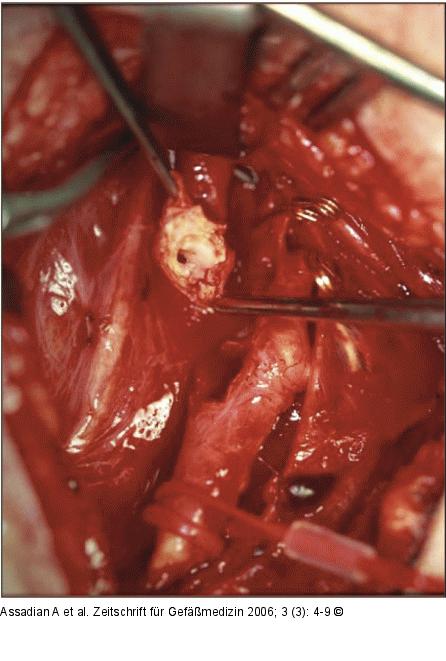

Abbildung 2b: Arteria carotis communis Nach Abklemmung der ACC, Arteria carotis interna (ACI) und externa. Absetzen der ACI. |

Nach Abklemmung der ACC, Arteria carotis interna (ACI) und externa. Absetzen der ACI. |